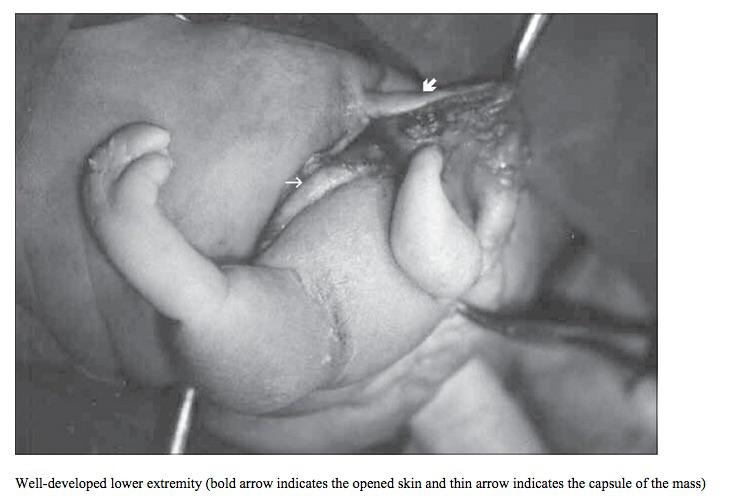

L’opération dure trois heures, au terme de laquelle ils extraient, avec stupeur, non pas un kyste, mais un fœtus « fossilisé », doté d’un visage, d’un œil, d’une dent et d’une longue chevelure brune, semblable à celle de Jenny Kavanagh. En fait, il s’agit là de son jumeau, qui, pendant 45 ans, s’est développé à l’intérieur d’elle.

Le fœtus in fetu se distingue du tératome par sa composition, bien que pendant longtemps, le premier ait été considéré comme une déclinaison du second. Le tératome est une tumeur bégnine constituée de cellules « pluripotentes », sorte d’héritage de la période embryonnaire où ce type de cellules est destiné à devenir des tissus (os, cheveu, muscle…).

Le fœtus in fetu, lui, présente déjà une organisation telle que l’on peut y observer des vertèbres, des membres ou encore des tissus organiques (dents, ongles, cheveux...). Il se nourrit de son environnement (en l’occurrence, un ovaire), mais, bien sûr, il n’a ni cœur battant, ni sang circulant.

Pour Jenny Kavanagh, la nouvelle a été difficile à encaisser, notamment parce que le fœtus était particulièrement développé. A son réveil, les chirurgiens lui ont montré une photo de la masse extraite. « Je me suis sentie triste quand je l’ai vu, parce qu’il a presque la taille et le poids d’un bébé. Le fait qu’il ait des longs cheveux comme moi (…) a renforcé cette impression. Mais je me dis qu’il m’aurait très probablement tuée si on ne me l’avait pas retiré ». A tout moment, le fœtus risquait en effet de se décrocher.